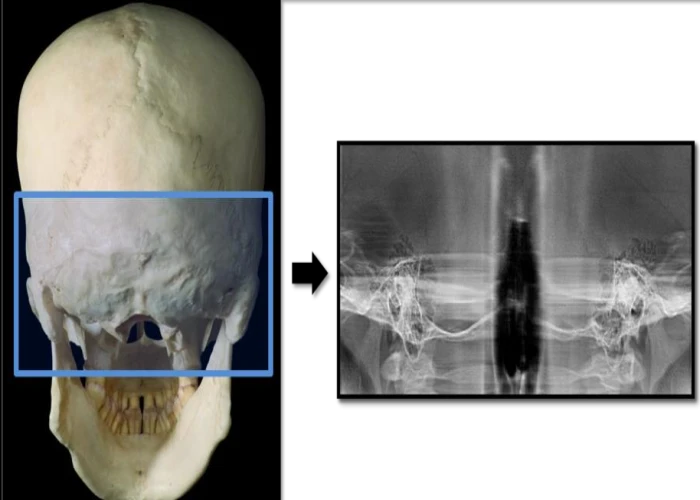

Oral Medicine & Radiology is concerned with diagnosis and medical management of diseases specific to the oral & maxillofacial structures, management of oral manifestations of systemic diseases, management of behavioral disorders, and dental treatment of medically compromised patients. It deals with the diagnostic intraoral and extraoral imaging of maxillofacial structures by both conventional and digital methods. It further includes Forensic Odontology and also promotes tobacco cessation.

Oral Radiologists deals with the diagnostic intraoral and extraoral imaging of maxillofacial structures which includes both conventional and digital imaging where as a General Radiologists deals with the imaging of the rest of the body with the same modalities.

4.CBCT, 3D Printing & Surgical & Endo Guide assisted management.